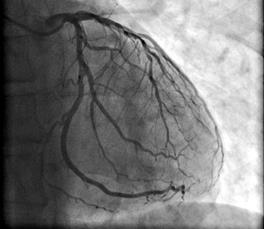

Рентгенографія серця (мал. 2 Б) – простий метод діагностики, який дозволяє оцінити розташування серця і його фізичні параметри. Знімок роблять в бічній і прямій проекції. Для візуалізації задньої межі серця може знадобитися введення контрастної речовини. Дослідження проводять за підозри на вади органу та для спостереження за малим колом кровообігу.

мал 9 Серце

Мал. 2 Б. Рентгенографія серця